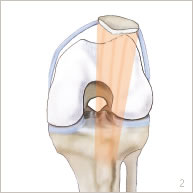

Par la suite, une incision d’environ 5 cm est réalisée à la partie supérieure du tibia. La tubérosité tibiale antérieure est exposée puis sectionnée (figure 3). Elle est ensuite translatée et repositionnée au milieu du tibia puis fixée par deux vis (figures 4 et 7).

Ces deux gestes permettent de bien repositionner la rotule au milieu de la trochlée et de la stabiliser.